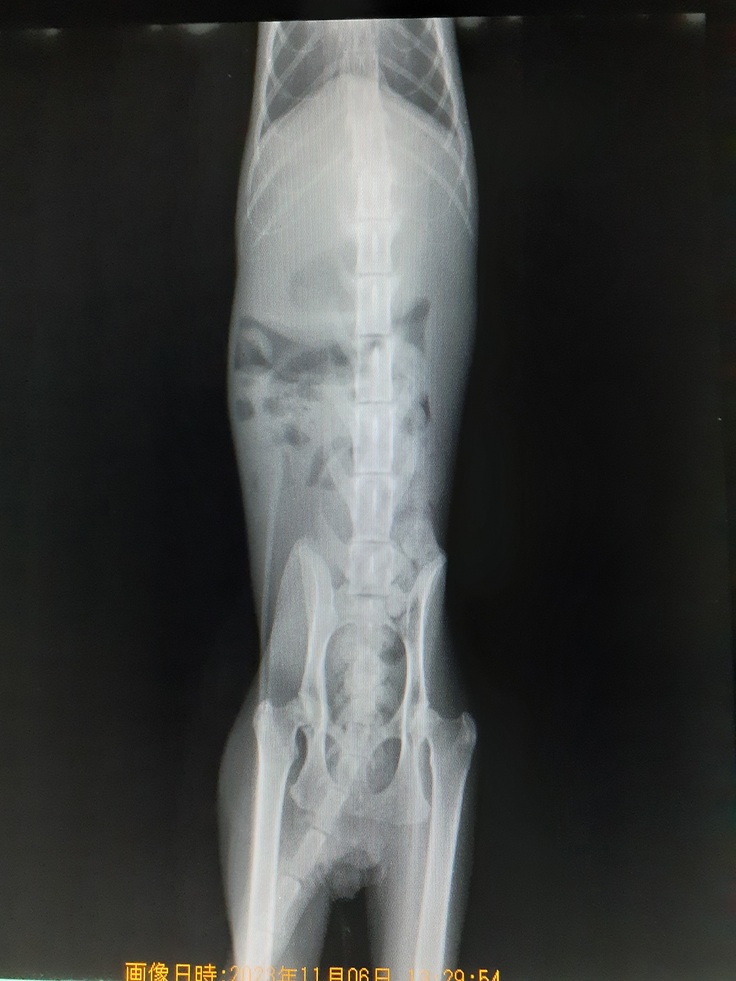

【ふうま君】は昨日保健所から引き受けてからすぐに動物病院にて初期医療を済ませました。

下半身不随の状態もレントゲンにて確認してきました。

背骨の3つと4つ目の骨が骨折していました。

既にねこ活にいる下半身不随の【くるみちゃん】は3つ目の骨折でしたのでそれよりは酷い状態を確認いたしました。

思い出して比べて見れば初期の麻痺の状態が【ふうま君】の方が少し酷くかんじています。

病院では大分酷い事故であったことを血液検査、レントゲンにて説明していただきました。